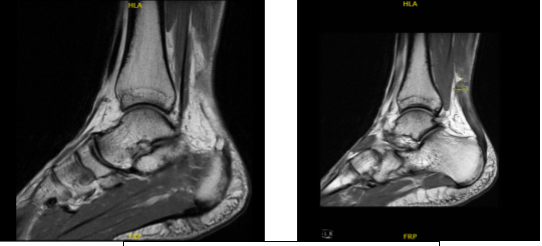

Because of the pain he experienced, we agreed to do an MRI to know where the pain was coming from.

MRI were reviewed and discussed, the soft tissues have significant posterior soft tissue swelling and edema secondary to Achilles tendon pathology. The bone marrow has a mild edema in the anterior tibial plafond and. No fracture or avascular necrosis.

While the osteochondral lesion is none, the medial tendons-posterior tibialis tendinosis and tenosynovitis without tears and the remainder the medial tendons, anterior tendons and lateral tendons are unremarkable.

The lateral ligaments: Syndesmotic ligaments: evidence of remote sprain and thickening of the anterior tibiofibular Ligament. No acute syndesmotic injury. Anterior talofibular ligament: evidence of remote sprain with mild thickening and scarring but no acute injury.

Calcaneofibular ligament and Posterior talofibular ligament are unremarkable. Medial ligaments: Deltoid ligament, Tibio-spring ligament, Proper spring ligament are unremarkable. Lisfranc ligament and joint are both normal.

The Achilles Tendon: Full-thickness tear of the Achilles tendon 4.3 cm proximal to its attachment near the myotendinous junction/aponeurosis with significant underlying, the Tendinosis and marked thickening of the Achilles tendon with a 1 cm gap in the torn tendon fibers.

The Plantar Aponeurosis: Thickening of the central cord of the plantar aponeurosis without Edema compatible with the sequelae of prior plantar fasciitis which is now healed. Sinus Tarsi: Normal fat signal characteristics. Tarsal Tunnel: Normal without masses. Muscles: Normal signal and bulk without edema or atrophy.

Marked Achilles tendinosis with a full-thickness tear 4.3 cm proximal to its attachment at the myotendinous junction with a 1 cm gap and associated soft tissue swelling. Posterior tibialis tendinosis and tenosynovitis without tears.

Evidence of remote syndesmotic ligament sprain and remote anterior talofibular ligament sprain but no acute ligamentous injury. Sequelae of healed plantar fasciitis.

MRI-1.2T Left ankle non-contrast